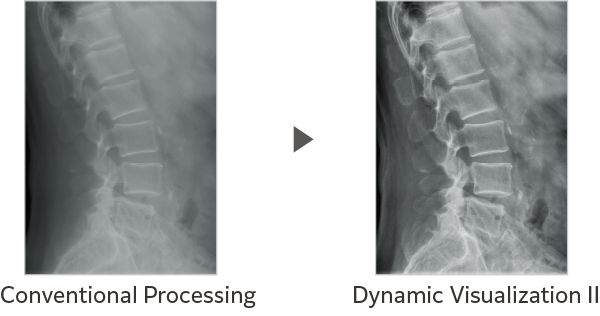

Dynamic Visualization II

Optimizes image quality using latest Exposure Data Recognizer

Advanced recognition algorithms using automatic  calculations of estimated 3D image data, identify the body part required and adjusts contrast, density and enhancement for optimised image display. (Option)

Comparison of Dynamic Visualization II vs. conventional processing images (Lumbar Spine)

Comparison of Dynamic Visualization II vs. conventional processing images (Hip Joint)